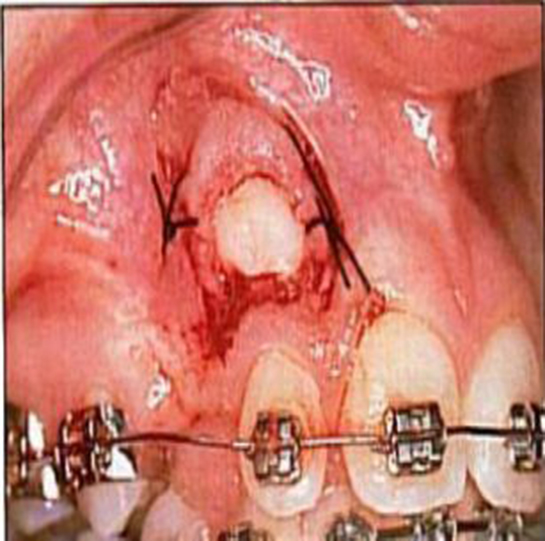

4. Travma ve Yaralanmalar Ağız içindeki travmalar veya yaralanmalar, üst damakta şişmeye neden olabilir. Bu durum, düşme, darbe alma veya ağızda sert bir nesne ile yaralanma sonucu ortaya çıkabilir.